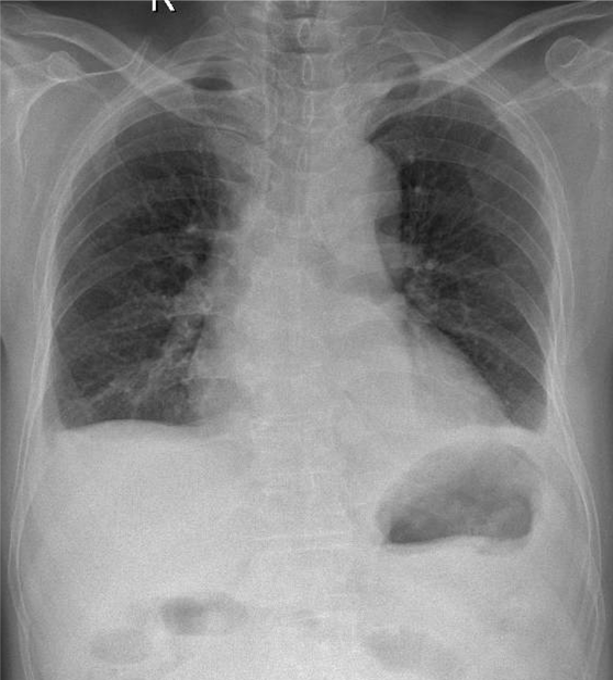

1-Góc carina rộng 2-Bóng tim to 3-Tràn dịch màng phổi hai bên lượng ít